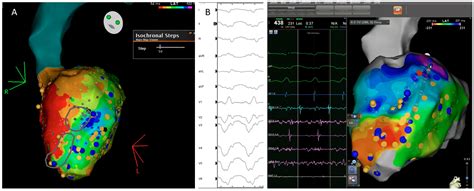

3. Mapping the Heart: The catheter is used to map the electrical activity of the heart. This helps the cardiologist identify the specific areas causing the abnormal heart rhythm.

4. Ablation: Once the problematic areas are identified, the catheter delivers radiofrequency energy or cryoenergy to destroy the abnormal tissue. This process is carefully monitored to ensure the correct areas are targeted.